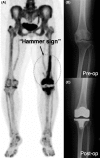

NaF PET assessment of bone metabolic changes around the femoral canal by intramedullary femoral alignment technique in total knee arthroplasty

We used the NaF PET scan to assess osteometabolic changes around the distal half of the femoral canal by intramedullary (IM) drill for femoral IM guiding rod insertion in total knee arthroplasty. Gentle IM rod insertion and focused attention can minimize surgical stress-induced biological reaction of the femoral IM canal.